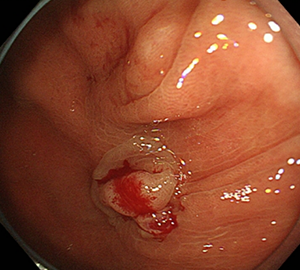

コールドスネアポリペクトミー(CSP)

合併症の非常に少ない優れた治療法であることから、近年大腸ポリープの外来切除法として急速に施行件数が増えてきています。当院ではこのコールドスネアポリペクトミーを主体としたポリープ切除を行っています。

| 1:ポリープを見つけます。 | 2:狭帯域光画像併用拡大観察で詳細に観察します。 | |

| 3:病変をスネアに通します。 | 4:周囲の正常粘膜をしっかり入れながら、病変を絞扼していき... | |

| 5:切除します。切除検体は吸引回収し病理検査を行います。 | 6:切除後に洗浄・観察して、病変の遺残ががないことを確認します。 |